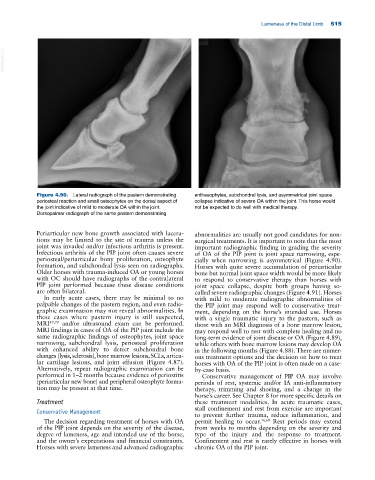

Figure 4.90. Lateral radiograph of the pastern demonstrating enthesophytes, subchondral lysis, and asymmetrical joint space

periosteal reaction and small osteophytes on the dorsal aspect of collapse indicative of severe OA within the joint. This horse would

the joint indicative of mild to moderate OA within the joint. not be expected to do well with medical therapy.

Dorsopalmar radiograph of the same pastern demonstrating

Periarticular new bone growth associated with lacera- abnormalities are usually not good candidates for non-

tions may be limited to the site of trauma unless the surgical treatments. It is important to note that the most

joint was invaded and/or infectious arthritis is present. important radiographic finding in grading the severity

Infectious arthritis of the PIP joint often causes severe of OA of the PIP joint is joint space narrowing, espe-

periosteal/periarticular bony proliferation, osteophyte cially when narrowing is asymmetrical (Figure 4.90).

formation, and subchondral lysis seen on radiographs. Horses with quite severe accumulation of periarticular

Older horses with trauma‐induced OA or young horses bone but normal joint space width would be more likely

with OC should have radiographs of the contralateral to respond to conservative therapy than horses with

PIP joint performed because these disease conditions joint space collapse, despite both groups having so‐

are often bilateral. called severe radiographic changes (Figure 4.91). Horses